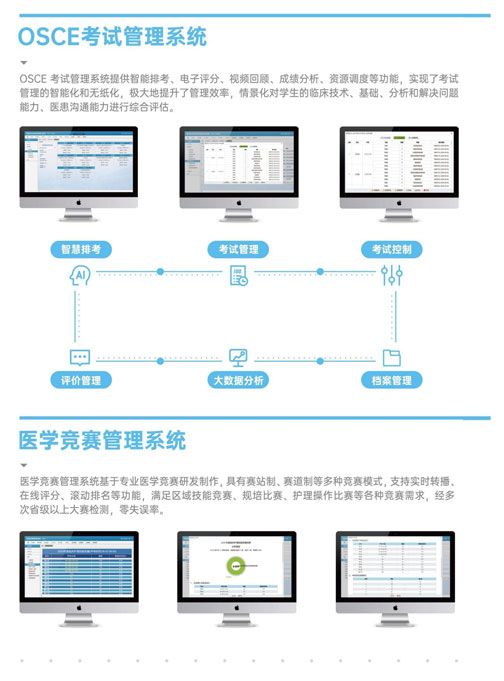

OSCE考试管理系统

OSCE考试管理系统